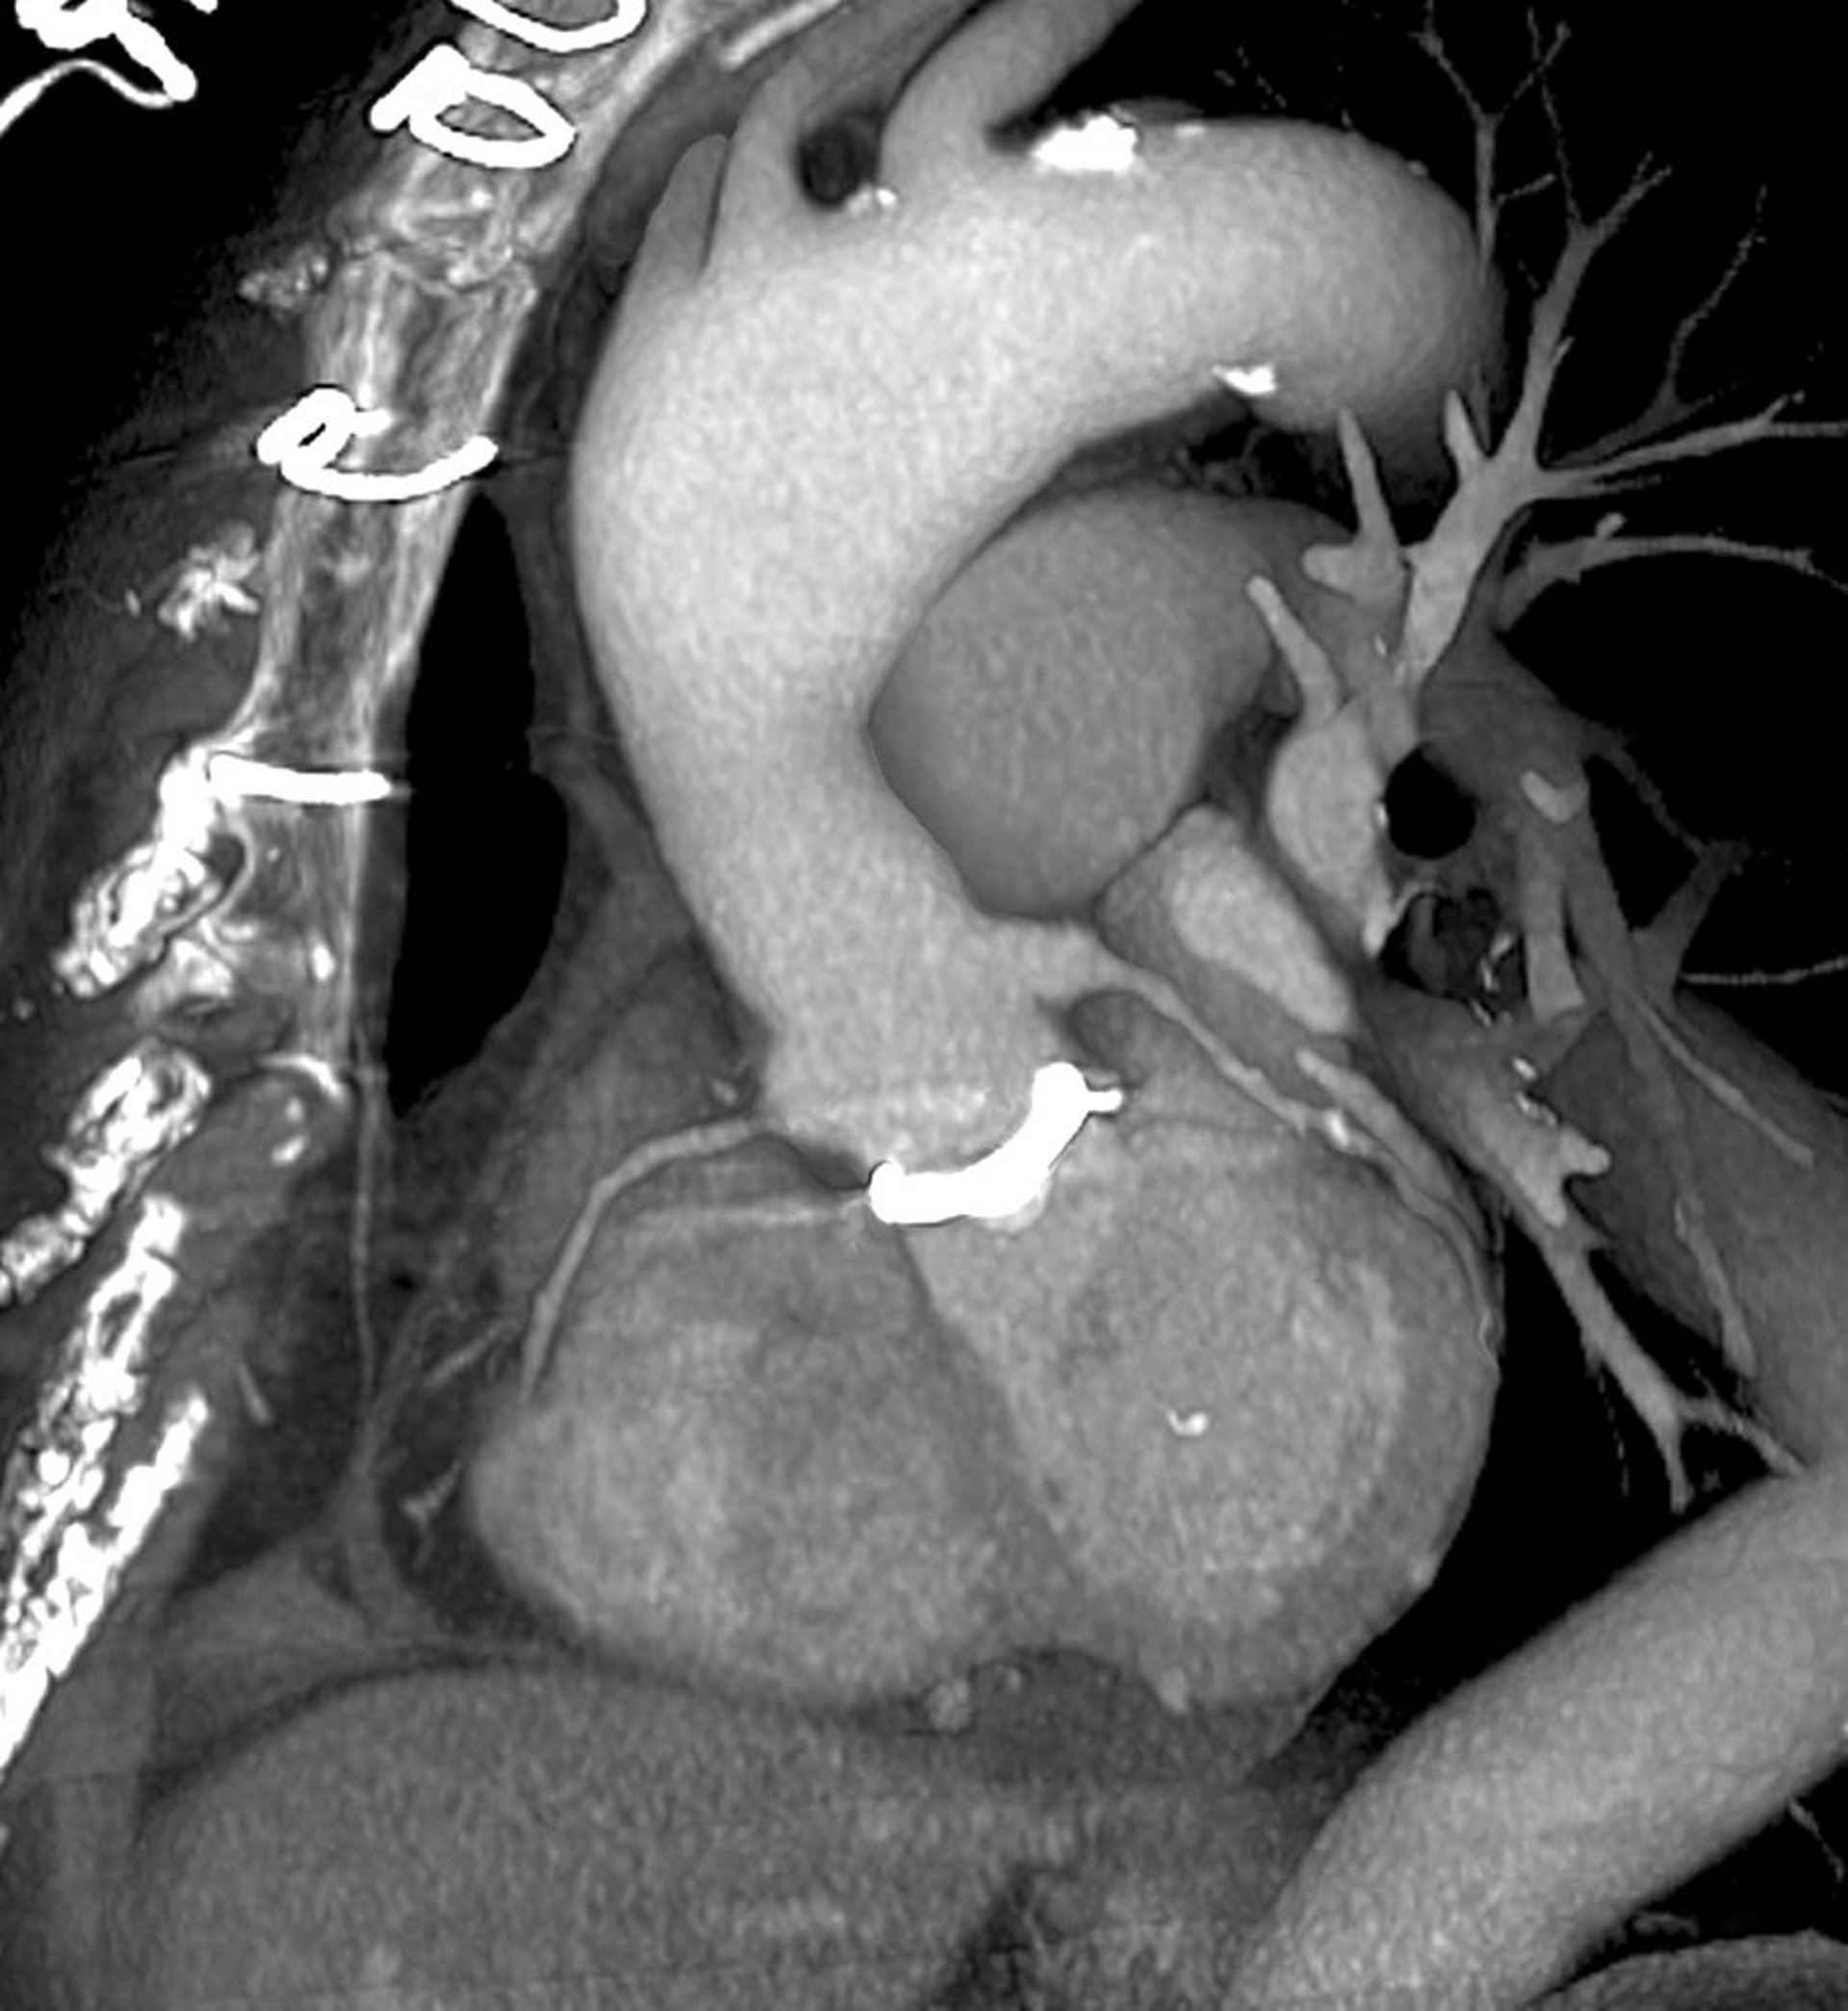

TDM cardiaque (scan 3D de prothèse valvulaire cardiaque)

Ceci est une vue oblique gauche, en regardant vers l'avant du thorax (à gauche). La valvule cardiaque prothétique (blanche) est visible au centre, où l'aorte (centre supérieur) rencontre le cœur (centre inférieur). Les points de suture utilisés pour fermer le thorax sont visibles en haut à gauche.

ZEPHYR/SCIENCE PHOTO LIBRARY